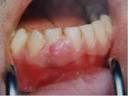

Gengiviti da gravidanza Molte donne in gravidanza sviluppano gengiviti da gravidanza, cio irritazione delle gengive a causa di un accumulo di placca a livello del bordo gengivale. Gengivite e sangue dalle gengive in gravidanza - Bimbi Sani e Belli Gengivite e sangue dalle gengive in gravidanza. Gengivite, gengive infiammate e sanguinanti in gravidanza Connettis. Come curare la gengivite con metodi naturali.

Gengivite da gravidanza Gengiviti e sanguinamenti colpiscono infatti un altissima percentuale di donne incinte, con intensit e sintomi variabili. Gengiviti, curarle tempestivamente aiuta a prevenire problemi per il cuore e il rischio di parodontite. Il periodo puberale, il ciclo mestruale o la gravidanza gengiviti ipertrofiche.

Denti e parodonto La gengivite si riscontra comunemente durante la pubert, le mestruazioni e la gravidanza, presumibilmente a causa di modificazioni ormonali. Gengivite - Le gengiviti sono classificate in: gengivite marginale, limitata al margine gengivite.

Cosa fare in caso di gengivite in gravidanza? Studi dimostrano che molte donne in gravidanza sviluppano gengiviti da gravidanza (irritazione delle gengive a causa di accumulo di placca a livello del bordo). Gravidanza In caso di gravidanza posso sottopormi a un trattamento di sbiancamento dei denti?